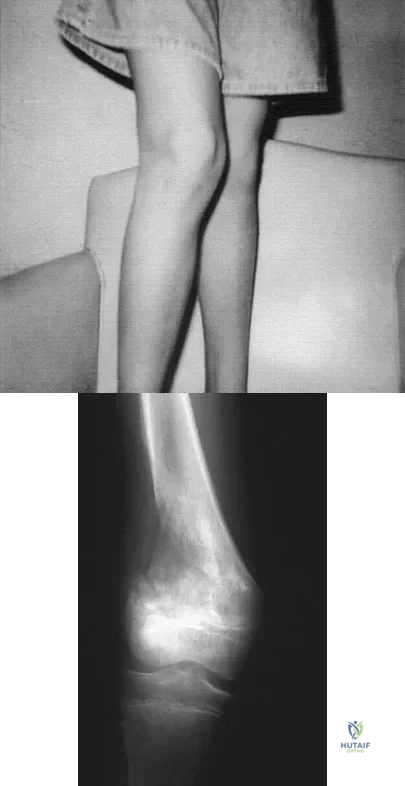

A 13-year-old girl is referred for a painful progressive valgus deformity of the right knee. Examination reveals an antalgic gait with an obvious valgus deformity. The right distal femur has a palpable, tender mass with erythema and warmth. Figures 4a and 4b show a clinical photograph and a radiograph. Management should consist of